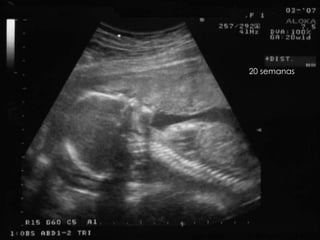

20 semanas